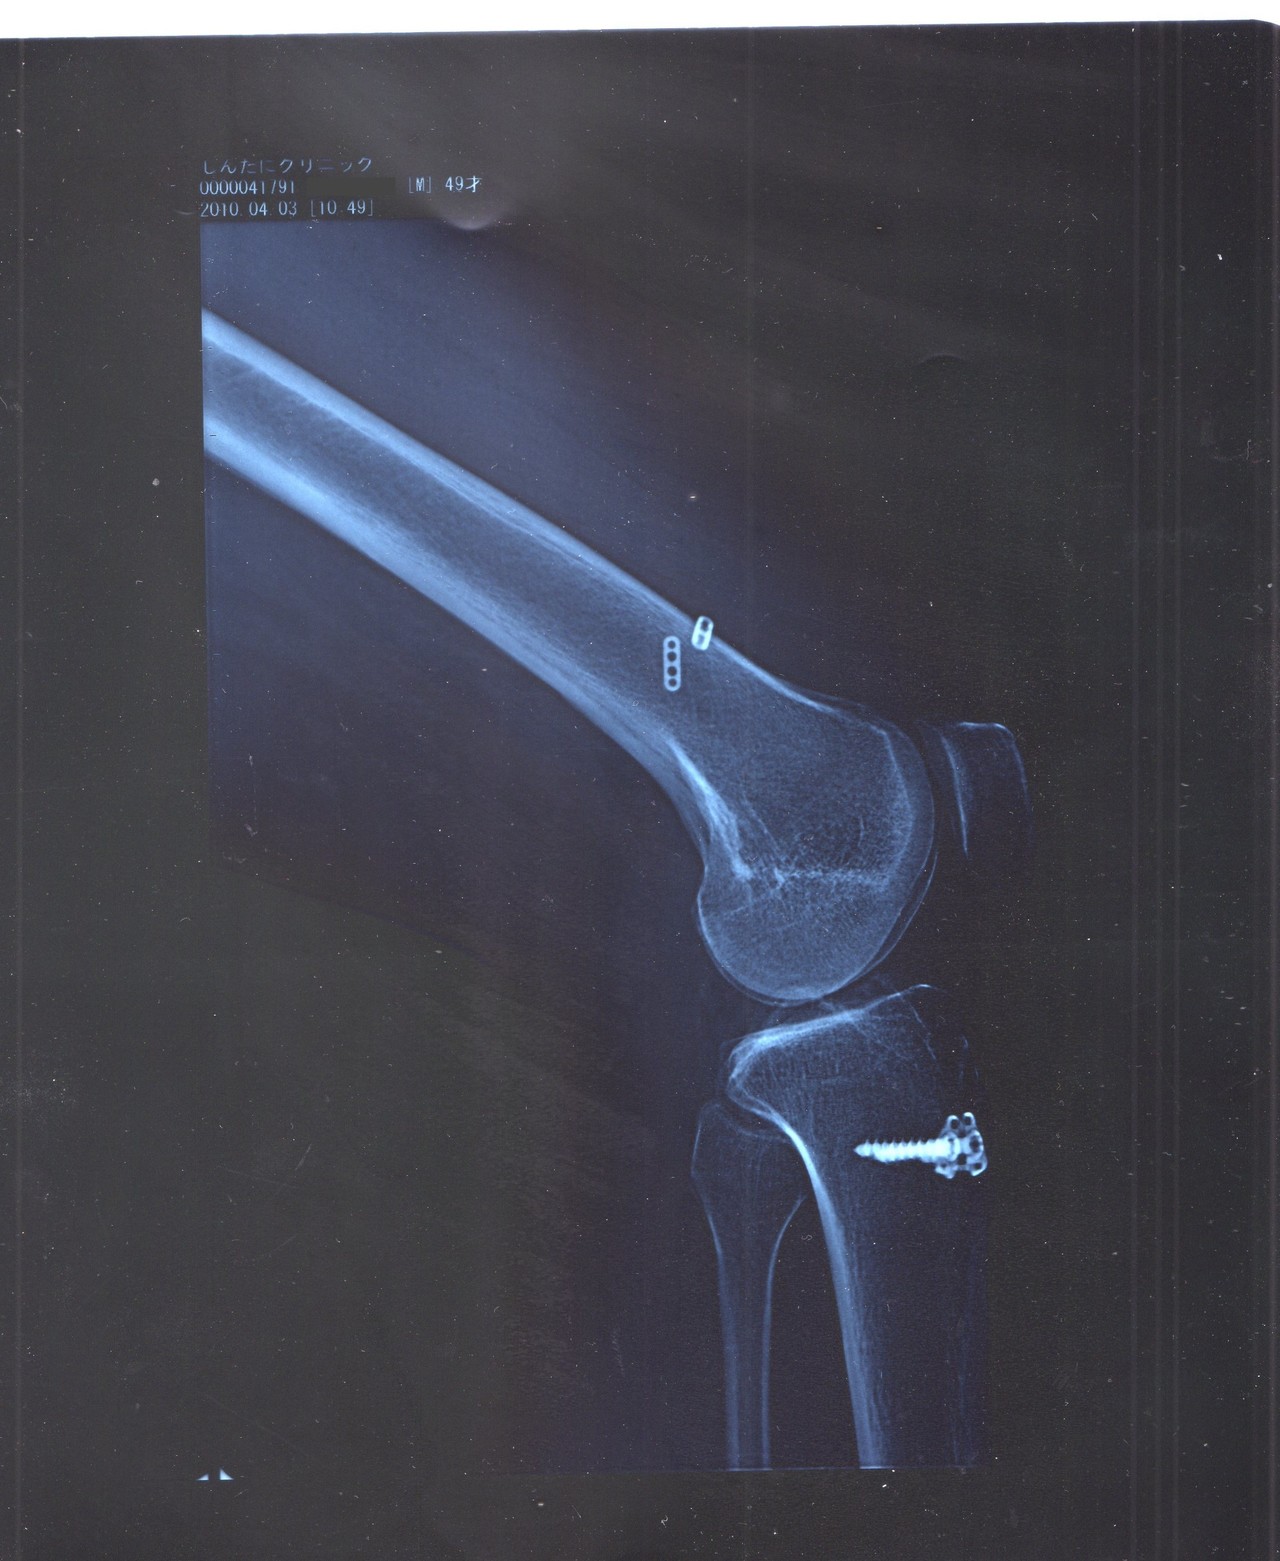

前十字靭帯断裂 サポーター-楽天市場「膝 後 十字 靭帯 サポーター」705件 人気の商品を価格比較・ランキング・レビュー・口コミで検討できます。ご購入でポイント取得がお得。セール商品・送料無料商品も多数。「あす楽」なら翌日お届けも可能です。前十字靭帯と後十字靭帯を断裂しました。二回の手術後の様子です。補強テープと膝サポーターの併用で、歩行ができるようになります。その後、 急速に膝が回復して2週間後にお仕事に復帰しました。 使用した膝サポーターは、 エクスエイドニーpcl です。